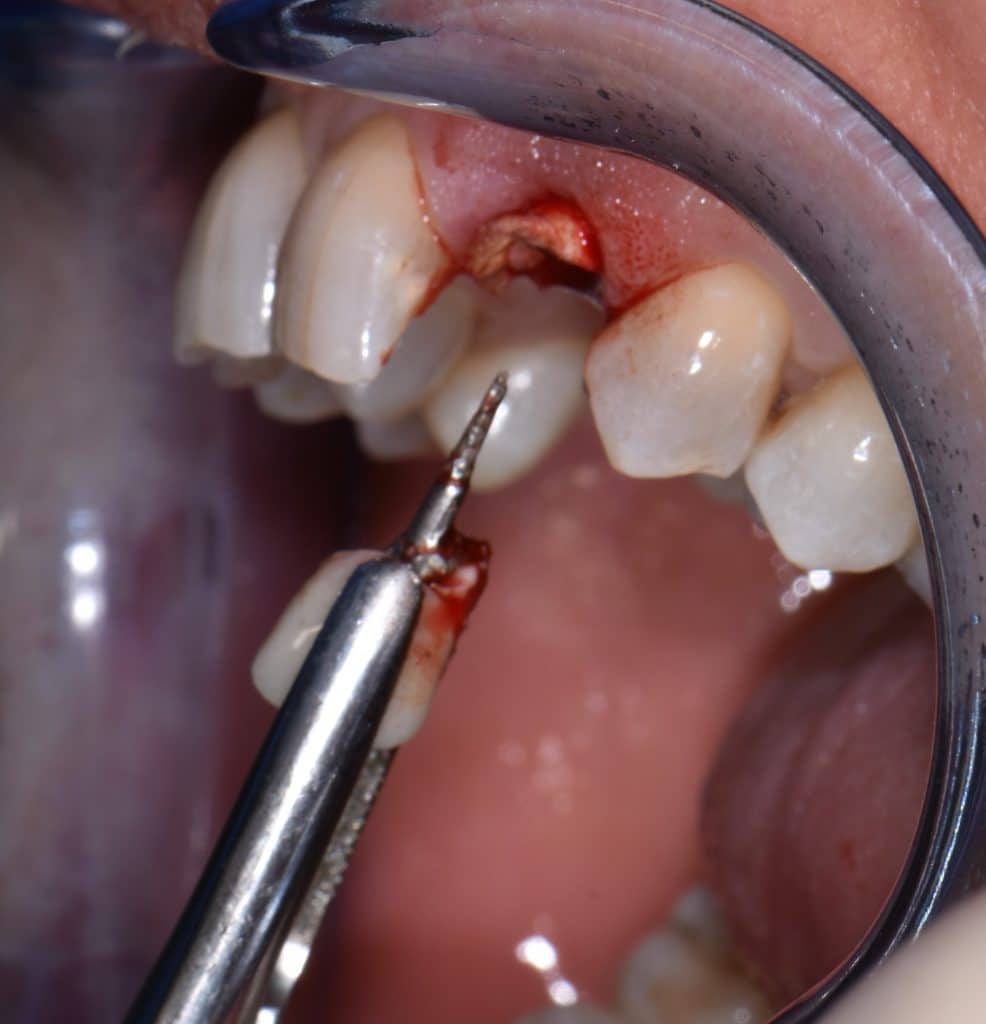

La pz N.G. di anni 52 (ASA 1) viene visitata nel mese di settembre 2017 per la mobilità ed inestetismo dell’elemento protesico 22, (foto iniziali sequenza 1) si evidenzia una frattura parziale della radice, si decide per l’estrazione ( foto sequenza 2) e sostituzione dell’elemento con un restauro implanto-protesico. Purtroppo la scarsa quota ossea apicale all’alveolo post-estrattivo (foto 2 rx) e l’alta valenza estetica dell’elemento ci rende cauti e si programma una socket preservation post estrattiva con l’ausilio delle membrane di prf (foto prf e socket sequenza 3 e 4). Durente i 5 mesi di guarigione la pz porta una protesi parziale mobile (foto 5,2) , a guarigione del sito post estrattivo si evidenzia una buona conservazione dei volumi osseo-gengivali,(foto guarigione sequenza 6) se pur presente una recessione distale all’elemnto 21.Nel mese di febbraio 2018 si procede all’inserimento di un impianto max-stability 3,75x12mm disegnando un lembo anticipato palatino per consentire un aumento dei tessuti vestibolari suturando con tecnica rool flap e trasformando l’elemento parziale mobile in una corona singola a carico immediato sul moncone temporameo applicando i concetti protesici bopt , (foto impianto moncone protesi provvisoria sequenza foto 7-8-9). Durante il periodo di maturazione dei tessuti molli vengono apportate opportune modifiche ai profili del provvisorio al fine di dare maggior spazio al tessuto gengivale, ( fotosequenza 10).Dopo circa 2 mesi dal protesizzazione provvisoria si è proceduto alla realizzazione del manufatto protesico con tecnica chair side sirona con l’ausilio del t-base (foto sequenza 11-12-13), realizzando in una sola seduta una corona in disilicato, ottenendo un risultato più che soddisfacente (Foto 14). Nel controllo a 3 mesi dal carico definitivo si apprezza la perfetta conservazione dei livelli ossei e gengivali. (foto sequenza 15).concludo con un follow up a 18 . Tengo a sottolineare che un caso come questo è stato conducibile con buoni risultati solo grazie alla piena fiducia della pz e alla sua massima motivazione e collaborazione. Ad oggi la pz sorride soddisfatta del risultato. E questo rappresenta la massima ricompensa di chi dedica tutto se stesso alla professione.